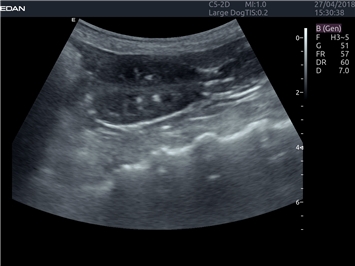

EDAN Acclarix LX4 VET

EDAN Acclarix LX4 VET представляет собой профессиональную ультразвуковую систему, специально разработанную для ветеринарных исследований. Сочетание стабильности, высокой производительности и эффективности делает эту систему идеальным выбором для современной ветеринарной практики.

• Универсальные датчики для различных видов животных

• Специализированные предустановки для ветеринарных исследований

• Гибкие протоколы исследований

• Расширенные возможности измерений